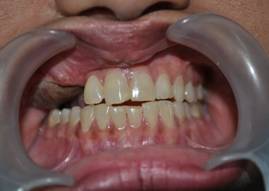

INTRA ORAL IMAGES

BALANCED OCCLUSION REHABILITATION